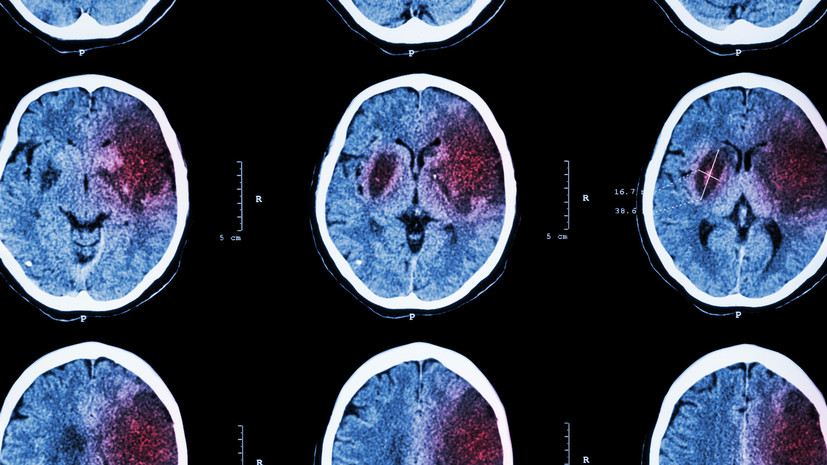

• Ишемический инсульт на компьютерной томографии

Учёные из Российского национального исследовательского медицинского университета имени Н.И. Пирогова и Национального медицинского исследовательского центра психиатрии и наркологии имени В.П. Сербского разработали препарат для реабилитации пациентов после инсульта. Лекарство эффективно даже при применении через сутки после кровоизлияния, что расширяет возможность оказания помощи пациентам. Ранее считалось, что эффективна только та терапия, которая оказывается в течение первых шести часов после инсульта. Исследование проводилось при поддержке Российского научного фонда (РНФ). Результаты опубликованы в журнале Molecules.